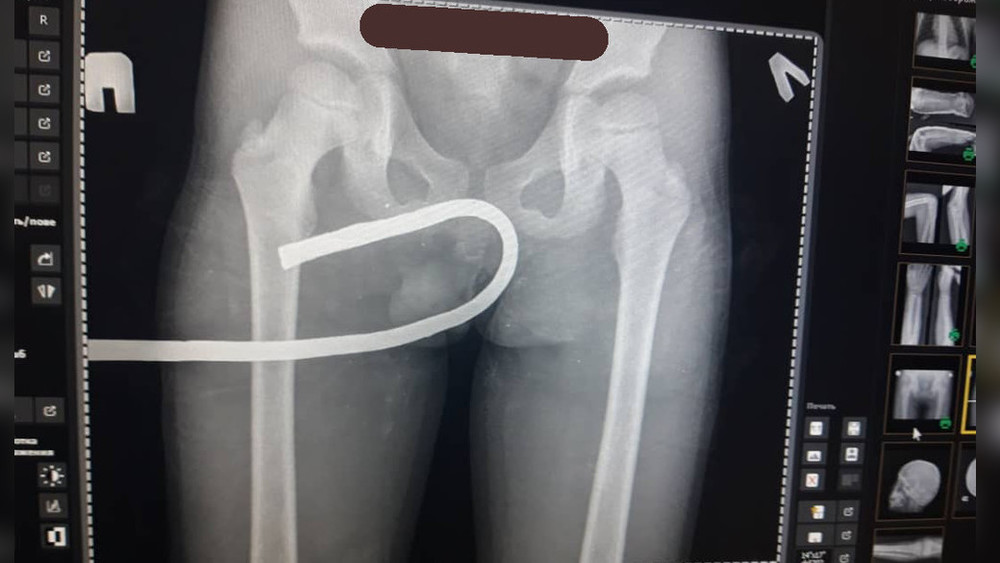

В Оше врачи вытащили из тела 7-летнего мальчика штырь. Фото

В Оше в живот 7-летнего ребенка воткнулся острый металлический предмет